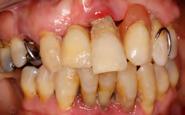

Figura 8-11. Imágenes de la planificación del cone-beam dentral tras el cierre de los tejidos blandos (inserción temprana de los implantes). En ellos observamos la planificación de los implantes de 6.5 mm de longitud y de diámetro reducido y plataforma 3.0 que van a ser empleados.

Dentista y Paciente 18 Calidad y dirección